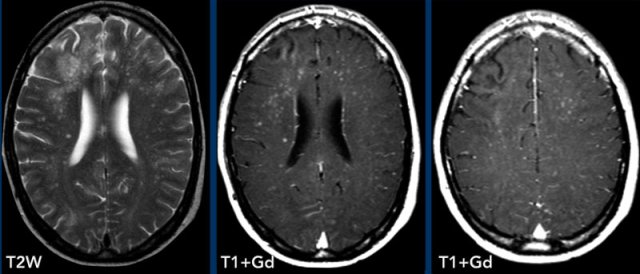

These examples show the advantage of FLAIR+Gd over T1W+Gd in a patient with lung cancer with cerebral metastases and carcinomatous meningitis.

Images

The FLAIR-image better shows the leptomeningeal enhancement around the pons (yellow arrow) and in the cerebellar foliae (black arrowheads).